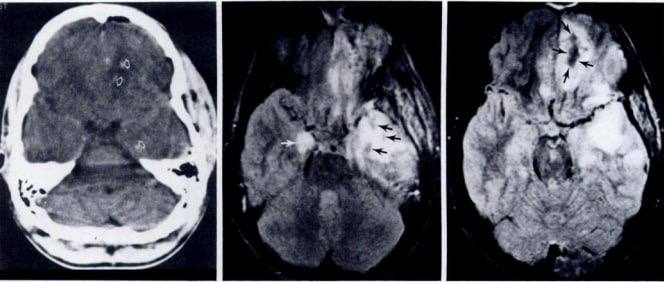

ضایعات بدخیم کبدی و مدیریت آنها: در میان ضایعات بدخیم کبد، کارسینوم هپاتوسلولار (HCC) شایعترین نوع سرطان اولیه کبد است که اغلب در بیماران مبتلا به سیروز یا عفونت مزمن ویروسی کبد دیده میشود. در تصویربرداری CT و